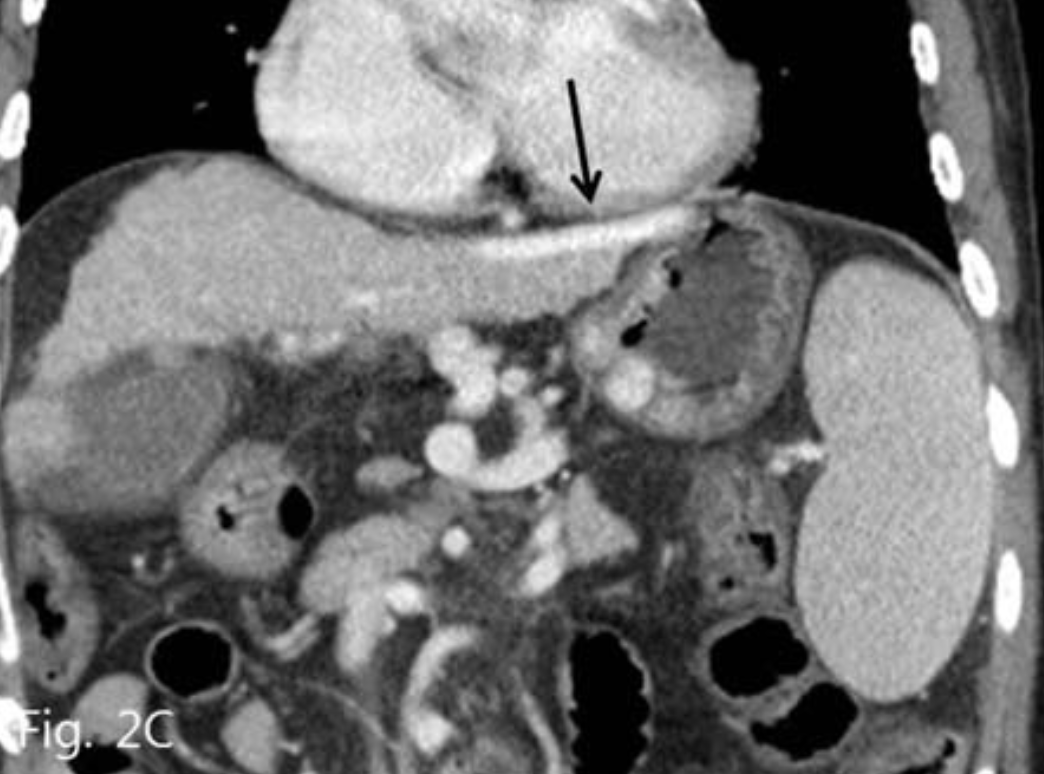

B형 간염에 의한 간경화 환자로 내원 하루 전 2차례의 토혈이 있어 내원하였다. 위내시경에서 식도 정맥류와 위정맥류가 동시에 관찰되었으며 내시경적 결찰술을 시행하였으나 그 후에도 위정맥류 부위에서는 지속적인 출혈이 있었다(Fig. 1).

Fig. 1

Endoscopy shows large gastric varices with active bleeding (arrow).